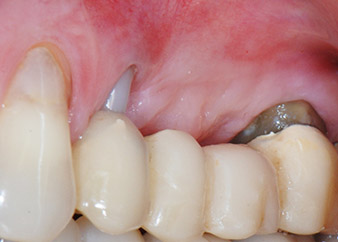

Une patiente de 58 ans se plaignait de douleurs et d'une mobilité accrue de la dent pilier 24 de son bridge. Présence d'une inflammation parodontale avec formation de poches de 7 mm de profondeur dans le sens mésiobuccal et de plus de 12 mm dans le sens distal, ainsi que d'une atteinte de la furcation au troisième degré. La radiographie a par ailleurs révélé une lésion parodontale étendue autour de la région apicale de la dent 24 ayant préalablement reçu un traitement endodontique (alio loco) (Fig. 1).

Un mois plus tard, le jour de l'intervention, la douleur et l'inflammation sur la dent 24 étaient minimes mais une mobilité de classe 2 de Miller était toujours observable. Après ouverture des lambeaux et nettoyage des tissus périapicaux et périradiculaires infectés, l'étendue du défaut osseux est devenue parfaitement visible (Figures 2 et 3).

À la racine de la dent, il manquait la totalité de l'os vestibulaire et distal. L'attache était essentiellement limitée à la racine palatine, venant ainsi confirmer le pronostic défavorable initial. La dent 27 présentait également une attache horizontale réduite et une raréfaction apicale minime (cf. Fig. 1), sans symptômes cliniques.